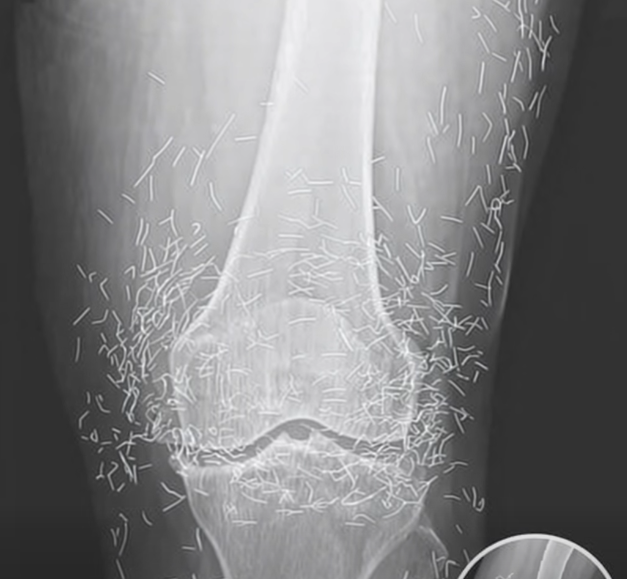

When a 65-year-old woman in South Korea visited the hospital for routine knee pain, she expected a familiar diagnosis: arthritis. Instead, her X-ray revealed a startling image—her knee joints were filled with tiny gold needles. The finding left doctors puzzled and opened a discussion about a lesser-known alternative treatment that had gone far beyond standard medical practice.

The woman had been living with osteoarthritis for years, a condition that causes joint stiffness and pain as cartilage gradually wears away. After traditional treatments and medication failed to provide relief, she turned to acupuncture, a popular therapy in many parts of Asia. However, her practitioner used a more unconventional method — leaving thin gold needles permanently inserted under the skin, believing they would offer lasting benefits.

While the intent was therapeutic, the results highlighted the risks of such procedures. Experts caution that leaving metal objects inside the body can trigger inflammation, infection, or interfere with diagnostic scans. In rare cases, they may even cause complications if a patient undergoes medical imaging like an MRI. Health professionals emphasize that while acupuncture can be helpful when performed correctly, permanent needle implants are not considered safe or evidence-based.